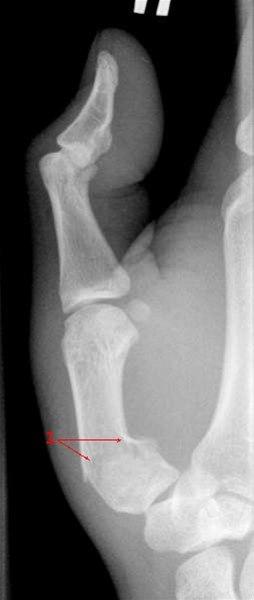

Metacarp 1 fraktur

Fraktur gjennom basis av første metacarp (1)